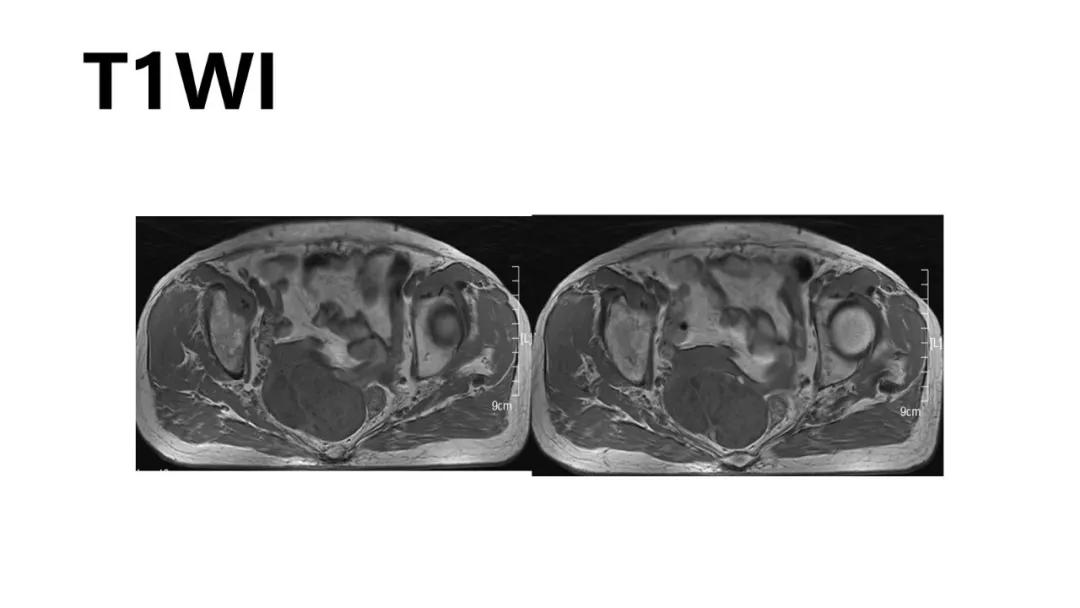

病例10

女,39 岁,体检发现盆腔肿块1月余

CA125:51U/ml

病理:左侧卵巢卵泡膜-纤维瘤